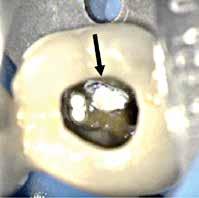

Fig. 15. Patienten blev (uden henvisning) opfordret til at fortsætte behandlingen på universitetstandklinik. Privatpraktiserende tandlæge havde påbegyndt rodkanalbehandling. A. Præoperativ røntgenoptagelse viser rodfyldt mesiofacial kanal. B. Klinisk foto efter fjernelse af midlertidig fyldning viser rodfyldning af MB1 og MB2 kanaler, furkal perforation (pil), instrumenteret distofacial kanal og palatinal kanal, som ikke er instrumenteret/fundet. C. Den furkale perforation blev lukket (pil), og den palatinale kanal blev lokaliseret og udrenset.

Fig. 15. Patient was advised (with no referral) to continue treatment at the University Dental Clinic. First maxillary molar had root canal treatment initiated by private practitioner. A. Preoperative radiograph showing root filled mesio-buccal canal. B. Clinical photo after removal of temporary restoration showing root filled MB1 and MB2 canals, furcation perforation (arrow), instrumented disto-buccal canal and uninstrumented/unlocated palatal canal. C. Furcation perforation was repaired (arrow), palatal canal located and instrumented.